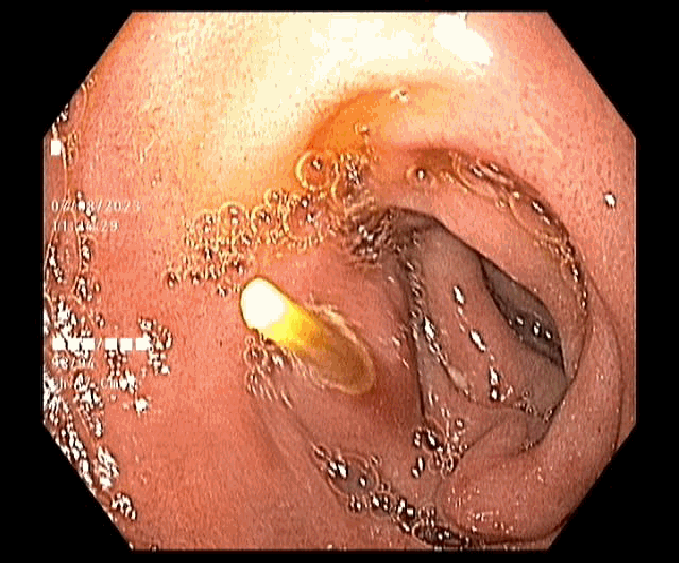

Nhận thấy tình trạng nguy cấp, ê-kíp nội soi ngay lập tức tiến hành nội soi an thần để gắp dị vật ra khỏi dạ dày của người bệnh. Sau khi thực hiện, các triệu chứng đau bụng đã thuyên giảm, ông Q. được tiếp tục theo dõi và xuất viện trong ngày.